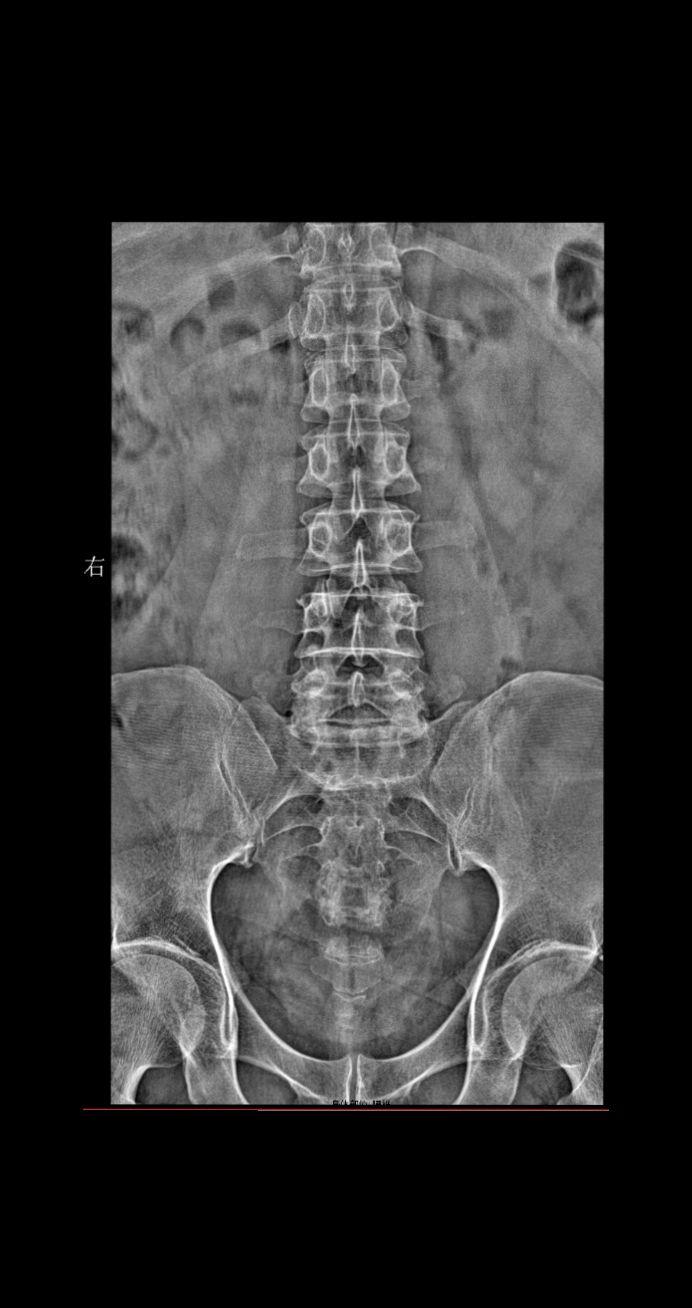

男 45 腰椎疼痛